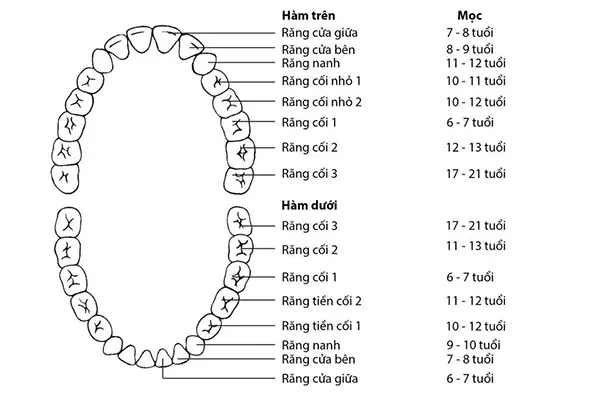

Các loại hàm răng là kiến thức cơ bản nhưng vô cùng quan trọng trong việc hiểu và chăm sóc sức khỏe răng miệng. Dù bạn đang

Câu hỏi “con nguoi co bao nhieu rang” luôn là thắc mắc phổ biến của nhiều người khi muốn hiểu rõ hơn về sức khỏe răng miệng.